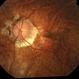

- Leukemic optic neuropathy

- Fundus photograph of an 18-year-old woman with Leukemic optic neuropathy.